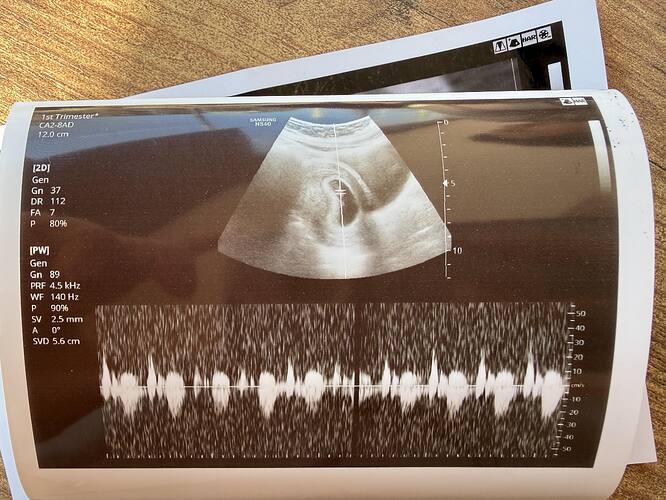

Bu yüzde 80 erkek bence

Siz ne diyorsunuz tahmininiz

Bacak arasından bir şey var Kordon ise ama kız bebek gibi duruyor canim